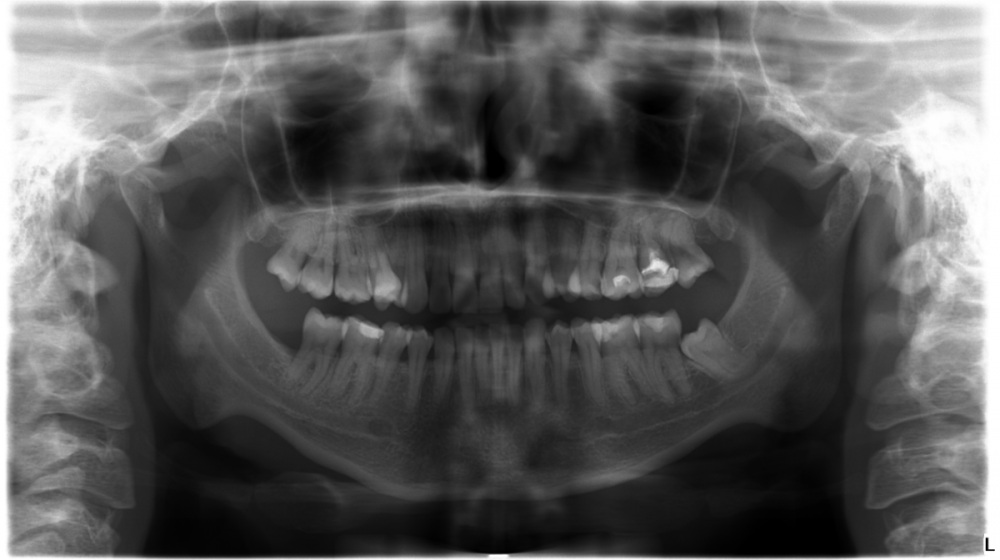

spectraitor Опубликовано 2 июля, 2023 Поделиться Опубликовано 2 июля, 2023 Здравствуйте! Планирую удаление трех оставшихся зубов мудрости, вызывает много вопросов нижний зуб. Один хирург сказал, что удаление хоть и сложное, но вполне выполняется амбулаторно. Другой утверждает, что удаление только в ЧХЛ. Вот КТ - https://disk.yandex.ru/d/KbeChDMj0QCtMg А также снимок. Подскажите, как лучше поступить? Может быть, можете посоветовать врача, который сможет удалить, не задев нервы (г. Москва)? Ссылка на комментарий